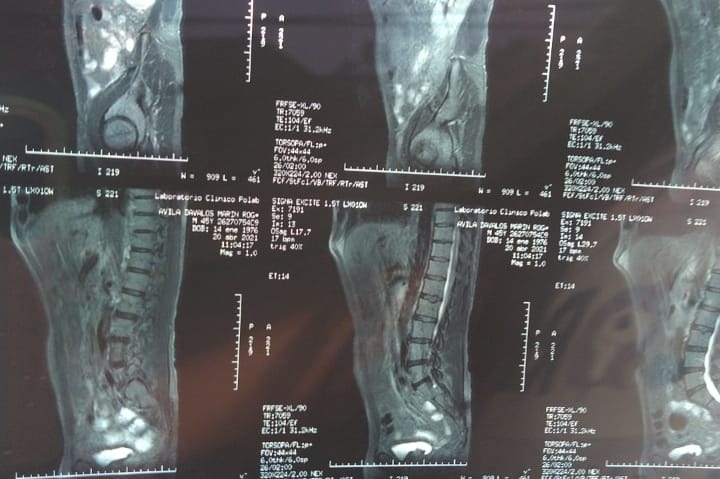

I never thought to do this but today I find myself in a very difficult situation. I want to be able to help my parents but I can't by myself. That is why my family and I ask for your help from the bottom of our hearts. My 55-year-old father with DM2 SAH (Type 2 Diabetes Mellitus and Hypertension) detected a large tumor two weeks ago that has been growing for many years. Known as Left Renal CA (Kidney Cancer) DX. My family and I have been going through very difficult times these past weeks since unfortunately we lost my Grandmother last month on April 14, 2021. A few weeks later we found out about the tumor that had been developing and forming in his body. Thanks to a fall he had and from which he began to shed blood, we decided to have him checked out because almost two years ago he had surgery to remove a hernia he had. When taking him to the clinic the Doctors decided to take tests to see what was going on in which his tumor was detected. Given the circumstances that we have gone through, my mother with the loss of my grandmother began to feel bad. So we also decided to take her to the doctor for a medical check-up in which they have also given us bad news since they have detected the development of a tumor in her throat and she also has symptoms of Diabetes. We are going through a very difficult and painful situation mentally and physically. We have had many medical expenses and there are many more expenses to come that we cannot afford like the surgery that my dad is going to need and the medical expenses that he and my mom will be faceing . We have seen several specialists with different opinions. But thank God we have found a doctor to operate on him on Monday May 10th, 2021. My family is a low-income family. That is why we are asking for your help to raise funds with all the medical expenses that my mom and dad will need. We have Faith in God and with the help of good people with you helping us with your prayers and donations we will be able to get through this difficult situation. Thank you very much and may GOD bless you and multiply you in every way.

Nunca pensé en hacer esto, pero hoy me encuentro en una situación muy difícil. Quiero poder ayudar a mis padres pero no puedo por mí misma. Es por eso que mi familia y yo pedimos su ayuda desde el fondo de nuestro corazón. Mi padre de 55 años con DM2 HAS (diabetes mellitus tipo 2 e hipertensión) detectó hace dos semanas un gran tumor que ha estado creciendo durante muchos años. Conocido como CA renal izquierdo (cáncer de riñón) DX. Mi familia y yo hemos pasado por momentos muy difíciles estas últimas semanas desde que lamentablemente perdimos a mi abuela el 14 de abril del 2021 el mes pasado. Unas semanas después nos enteramos del tumor que se había estado desarrollando y formándose en el cuerpo de mi papá. Gracias a una caída que tuvo y de la que empezó a derramar sangre, decidimos hacer que lo revisaran porque hace casi dos años lo operaron para extirpar una hernia que tenía. Al llevarlo a la clínica los médicos decidieron hacerle pruebas para ver qué estaba pasando en el que se detectó su tumor. Dadas las circunstancias por las que hemos pasado, mi madre con la pérdida de mi abuela empezó a sentirse mal. Así que también decidimos llevarla al médico para un chequeo médico en el que también nos han dado una mala noticia ya que han detectado el desarrollo de un tumor en su garganta y también tiene síntomas de Diabetes. Estamos atravesando una situación muy difícil y dolorosa mental y físicamente. Hemos tenido muchos gastos médicos y hay muchos más gastos por venir que no podemos afrontar, como la cirugía que va a necesitar mi papá y los gastos médicos que él y mi mamá tendrán que afrontar. Hemos visto a varios especialistas con opiniones diferentes. Pero gracias a Dios hemos encontrado un médico para operarlo el dia Lunes 10 de Mayo 2021. Mi familia es una familia de bajos ingresos. Por eso les pedimos su ayuda para recaudar fondos con todos los gastos médicos que necesitarán mi mamá y mi papá. Tenemos Fe en Dios y con la ayuda de buenas personas cono usted en ayudándonos con tus oraciones y donaciones podremos superar esta difícil situación. Muchas gracias y que DIOS te bendiga y te multiplique en todos los sentidos.